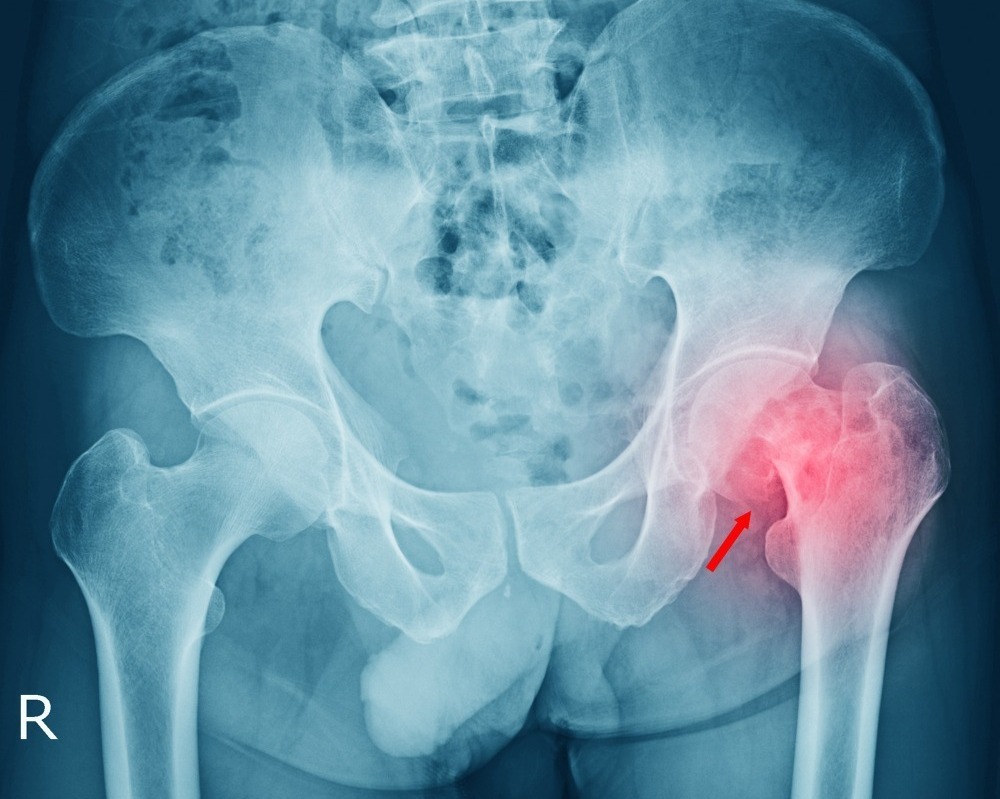

Chondrosarcoma Surgery in Mumbai – Restoring Strength Through Specialized Care